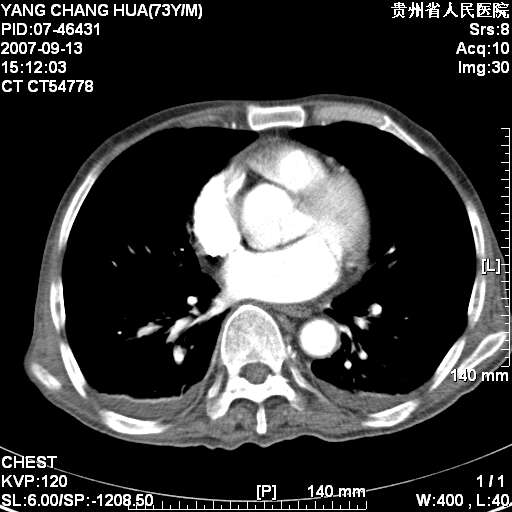

图像没有传全。肺部为感染性病灶;肺囊肿;双侧胸腔积液;肝脾肿大;腹水。

双肺部为感染性病灶.双侧胸腔积液;肝脾肿大;腹水.

双肺部为感染性病灶.双侧胸腔积液;肝脾肿大;脾脏密度不均,不除外脾侵润?腹水.

图片不全.就这几张图片.无法诊断淋巴瘤的,我考虑:双肺部为炎性病灶.双侧胸腔积液;肝脾肿大;腹水

双肺点片状影,以双上肺改变明显.双侧胸腔积液.为感染性病灶,但不除外结核.

肝脾都大..

双上肺继发型肺结核。

双侧胸腔积液。

肺大泡。

食管癌未除。

肝脾肿大。

少量腹水。

双肺散在斑片状及多发小结节状阴影,边缘模糊,双上肺野明显,双侧胸膜腔少量积液,纵隔及肺门区未见明显肿大淋巴结,肝脾肿大,脾内见多发低密度区,结合临床考虑恶性淋巴瘤(肺内表现为肺炎肺泡型),单看影像表现,肺结核不能排除。建议结合实验室检查或表浅淋巴结活检。

肺部为;恶性淋巴瘤;双侧胸腔积液;肝脾肿大;腹水。